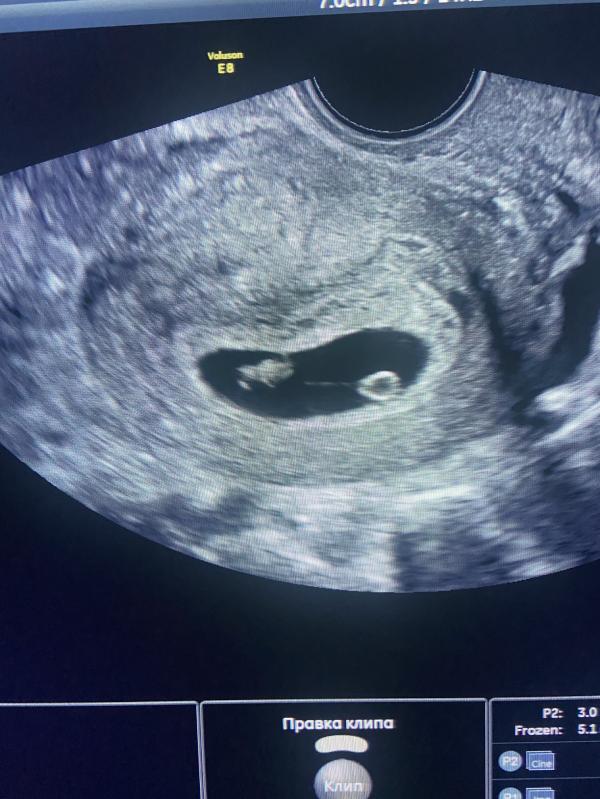

Моя вселенная ❤️ Малыш встретил меня с воздушным шариком 🌸 Крохе 7 недель 🙏🏽

Я об этом даже не подумала 😀🙏🏽 как объяснил врач в матке одно плодное яйцо🙏🏽 что это такое врач объяснил, я не очень поняла 😅 вернее была занята просмотром малыша 😇🌸❤️ может кто то сталкивался и ещё тут напишет 🙏🏽

Да, я не могла оторвать взгляд от экрана УЗИ 🙏🏽🌸 врач смеялся: «это что за комарик с воздушным шариком?» 😇😂

А воздушный шарик это что ?не второй ли ?))